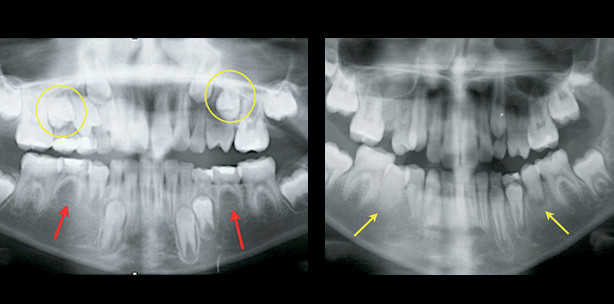

Oft sind transplantierte Prämolaren etwas kürzer als normale Zähne, ihre Wurzellänge ist um 10% bis 15% geringer. Wenn sie jedoch mit der halben Wurzellänge von normalen Zähnen oder kürzer transplantiert werden, sollten sie nach der Operation ein erhebliches Wurzelwachstum zeigen (Abb. 3). Deshalb können als die drei Hauptindikationen für eine erfolgreiche Autotransplantation von im Wurzelwachstum befindlichen Prämolaren die folgenden Aspekte zusam­men­gefasst werden: Pulpaobliteration, fortgesetztes Wurzelwachstum und Durchbruch des Transplantats, wenn es auf gingivaler Ebene transplantiert worden ist. Liegen diese Indikatoren nicht vor, wird gemäß der von Kristerson und Lagerström6 erstellten Kriterien die Autotransplantation nicht als erfolgreich bewertet. Wenn es keine anderen Behandlungsoptionen gibt, sollte dennoch erwogen werden, den transplantierten Prämolaren an dieser Stelle zu belassen. Der Patient sowie dessen Eltern sollten über etwaige postoperative Komplikationen und mögliche Behandlungsalternativen informiert werden. Die meistgenannten kieferorthopädischen Indikationen für eine Autotransplantation von im Wurzelwachstum befindlichen Prämolaren7 beziehen sich auf Patienten mit einer leichten Klasse II-Malokklusion und fehlenden Anlagen der unteren Prämolaren, Patienten, die aufgrund eines Traumas einen oder mehrere maxillare Schneidezähne verloren haben, sowie Patienten mit einer multiplen Agenesie. Solche Anomalien treten oft bei kiefer­orthopädischen Screenings von Patienten unter zehn Jahren auf, wo nicht durchgebrochene Prämolaren vorhanden sein können, die als Spenderzähne geeignet sind. Grundlage hierfür sind kieferorthopädische Indikationen, die deren Entnahme begünstigen. Die Autotransplantation von Prämolaren bei heranwachsenden Klasse II-Patienten mit fehlenden unteren Prämolaren kann erwogen werden, wenn es erstens kei­ne Milchmolaren gibt, die Zeichen einer fortgesetzten Wurzelresorption und damit einer Infraposition (Abb. 1a) oder verkürzte Zahnwurzeln aufweisen, und zweitens das Patientenprofil ei­ne Erhaltung der unteren Zahnbogenlänge und vorzugsweise die Extraktion der oberen Prämolaren erfordert. Abbildung 1 zeigt eine Panoramaaufnahme eines elf Jahre und sechs Monate alten Mädchens mit fehlenden Zahnanlagen der zweiten unteren Prämolaren und einer Infraokklusion der unteren Milchmolaren auf der linken Seite (Abb. 1a). Der Behandlungsplan sah die Au­totransplantation zweier nicht durchgebrochener oberer zweiter Prämolaren vor, um die zwei fehlenden unteren zweiten Prämolaren zu ersetzen (Abb. 1b). Kieferorthopädische Indikatoren implizierten Klasse II-Molaren- und Eckzahnbeziehungen auf beiden Seiten (Abb. 1c, g). Die oberen ersten Prämolaren auf der linken Seite waren übereruptiert. Sechs Monate nach der Operation brachen die transplantierten Prämolaren durch (Abb. 1d, h). Dies dauerte weitere sechs Monate an (Abb. 1e, i). Ein Jahr und acht Monate nach der Transplantation wurden im Zu­ge der kiefer­orthopädischen Behandlung festsitzende KFO-Geräte eingesetzt.

Heranwachsende Patienten mit schwer geschädigten oder avulsierten mittleren Schneidezähnen sind oft geeignete Kandidaten für eine Transplantation von im Wurzelwachstum befindli­chen Prämolaren. Wenn fehlende Vor­derzähne nicht durch Zahnersatz ersetzt wurden, welcher sich dem Wachstum anpasst, kann eine signifikante Resorption des alveolaren Knochens auftreten. Die­-se würde zukünftige Transplantationen nach abgeschlossenem Wurzelwachstum unmöglich machen. Die Vorteile der Autotransplantation von sich im Wurzelwachstum befindenden Prämolaren bei beschädigten Schneidezähnen sind nicht nur durch den sofortigen Austausch eines fehlenden Zahns oder fehlender Zähne gegeben. Sie begründen sich auch in ihrem Potenzial für Knochenregeneration, wenn ein Trauma den Alveolarenfortsatz beeinträchtigt oder eine Resorption des alveolaren Knochenkamms vorliegt. Die Abbildungen 2 und 3 zeigen Aufnahmen eines elfjährigen Patienten, der eine große Zyste an der Wurzelspitze des oberen linken mittleren Schneidezahns als eine pathologische Folge der Ex­traktion eines Mesiodens aufwies. Die Zyste wurde zusammen mit der Wurzel des oberen linken mittleren Schneidezahns chirurgisch entfernt, um nichtentzündliche Bedingungen für eine Autotransplantation zu schaffen und den fehlenden Zahn zu ersetzen. Zwei Wochen nach dem chirurgischen Eingriff wurde der nicht durchgebrochene obere rechte zweite Prämolar (Abb. 2c) transplantiert. Drei Monate nach der Transplantation war die Hei­-lung des Knochendefekts deutlich sichtbar (Abb. 2d). Auch im Verlauf der nächsten Monate, besonders nach fünf und neun Monaten (Abb. 2e, f), wurden diese beobachtet. Wurzelwachstum und Pulpaobliteration waren ebenfalls zu erkennen und deuteten auf eine normale Entwicklung des Transplantats hin. Weil der Platz im Implantationsbereich nicht ausreichte, wurde der Spenderzahn während der Operation um 180° gedreht (Abb. 2h). Vier Monate nach der Transplantation wurde ein temporärer Kompositaufbau angepasst, um die Morphologie des Schneidezahns nachzubilden (Abb. 2i). Die kieferorthopädische Behandlung ist nach dem Durchbruch aller bleibenden Zähne vorgesehen.

Bei Fällen mit starker Verla­gerung nicht durchgebrochener Prämolaren kann eine andere Implantatart verwendet werden, die transalveoläre Transplantation. Sie bezeichnet das chirur­gische Aufrichten eines Zahns von seiner anfänglich ektopischen zu einer normalen Position. Abbildung 3 zeigt eine Aufnahme eines verlagerten unte­-ren zweiten Prämolaren bei einem Mädchen von zwölf Jahren und fünf Mo­na­ten. Weil der Winkel zwischen der langen Zahnachse des ver­lagerten Zahns und den langen Achsen der Nachbarzähne mehr als 45° betrug, wurde eine transalveoläre Transplantation gewählt, um den unteren zweiten Prämolaren aufzurichten (Abb. 3a b). Dabei ist es für ei­ne erfolgreich verlaufende Zahnheilung entscheidend, den Spen­derzahn vorsichtig zu entfernen, ohne ein Trauma beim Spen­der­folli­kel zu verursachen. Dies ist aber bei transalveolären Trans­plan­tationen aufgrund der ursprünglichen ektopischen Positionierung des Spen­der­zahns besonders schwierig (Abb. 3e–g). Spenderzähne mit kürzeren Wurzeln und maximal der Hälfte der end­gültigen Wurzellänge werden be­­vorzugt, weil eine atraumatische Entfernung bei diesen Zähnen einfacher umzusetzen ist. Im vorliegenden Fall wird eine normal verlaufende Knochenheilung nach der Transplantation erwartet. Auch eine normale Entwicklung des transplantierten Prä­molaren einschließlich Wurzelwachstum und Zahndurchbruch ist zu erwarten (Abb. 1b–d, h, i). Ein weiterer Vorteil dieser Behandlungsalternative ist die signifikante Verringerung der Behandlungsdauer in Relation zur kieferorthopädischen Traktion. Bei Fällen mit stark verlagerten, nicht durchgebrochenen Prämolaren und einer schlechten Prog­nose für die kieferorthopädische Traktion stellt sie sogar die einzige Alternative zur Zahnextraktion dar. Die Autotransplantation von sich im Wurzelwachstum befindenden Prämolaren kann erfolgreich bei Patienten mit fehlenden An­lagen für Prämolaren oder aufgrund eines Traumas fehlenden oberen Schneidezähnen durch­geführt werden, sofern entsprechende kieferorthopädische und chirurgische Indikationen vorliegen. Die transalveoläre Transplantation kann im Falle eines chirurgisch aufgerichteten verlagerten Prämolaren angewendet werden. Eine gute Kommunikation und Zusammenarbeit zwischen Kieferorthopäde und Oralchirurg ist maßgeblich für ein erfolgreiches Ergebnis. Bei einer Transplantation von sich im Wurzelwachstum befindenden Prämolaren zur anterioren Maxilla sollte auch ein Prothetiker einbezogen werden. Eine umfassende Nachsorge nach erfolgter Transplantation kann zudem wertvolle Informationen über die Heilung von Pulpa und Zahnfleisch vermitteln.